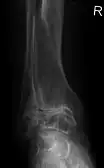

Diagnosis is made with reasonable certainty based on history and clinical examination.[52][53] X-rays may confirm the diagnosis. The typical changes seen on X-ray include: joint space narrowing, subchondral sclerosis (increased bone formation around the joint), subchondral cyst formation, and osteophytes.[54] Plain films may not correlate with the findings on physical examination or with the degree of pain.[55]

Severe osteoarthritis and osteopenia of the carpal joint and 1st carpometacarpal joint